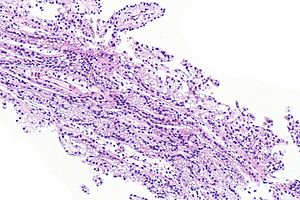

Prostatic-type polyp. H&E stain. (WC/Nephron) | |

| LM | benign prostatic type epithelium or transitional type epithelium +/-corpora amylacea |

| LM DDx | prostatic ductal carcinoma |

| IHC | PSA +ve |

| Site | urethra/prostate gland - verumontanum |

Prostatic-type polyp is an uncommon polyp of the genitourinary tract. It is typically centered on the verumontanum of the prostate gland and projects into the urethra.

Features:[2]

- Benign prostatic type epithelium or transitional type epithelium.

- Cuboidal to low columnar cells with basal cell layer.

- +/-Corpora amylacea.